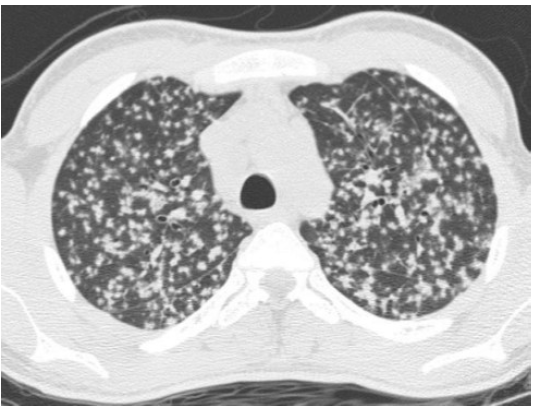

FIBROSI POLMONARE

Descrizione: Parenchima polmonare con aumento della trama alveolare per fibrosi dei setti.